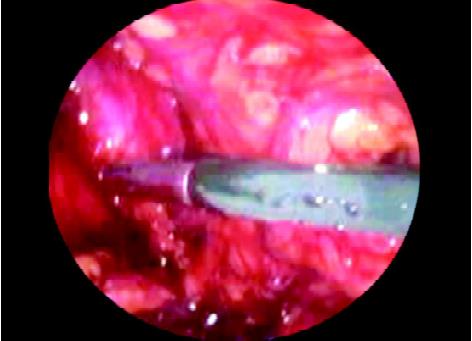

Dissection of Preperitoneal Space and Cord Structures in TEP

In the totally extraperitoneal repair of hernia Stoppa's parietalization technique is used for dissection of the spermatic cord from the peritoneum by separating the elements of the spermatic cord from the peritoneum and peritoneal sac should be done. The dissection is started by tracing the inferior epigastric vessels towards the deep ring. The upper border of the hernia sac readily recognized because indirect hernia is lateral to the inferior epigastric vessels and direct hernia is medial to that. As the inguinal region is approached, the dissection is continued all around the sac to encircle the neck. The surgeon should try to remain close to peritoneum and dissection continues medially to separate vas from the sac. Under the neck of the sac, care should be taken to avoid injury of iliac vessels.

Dissection of preperitoneal space